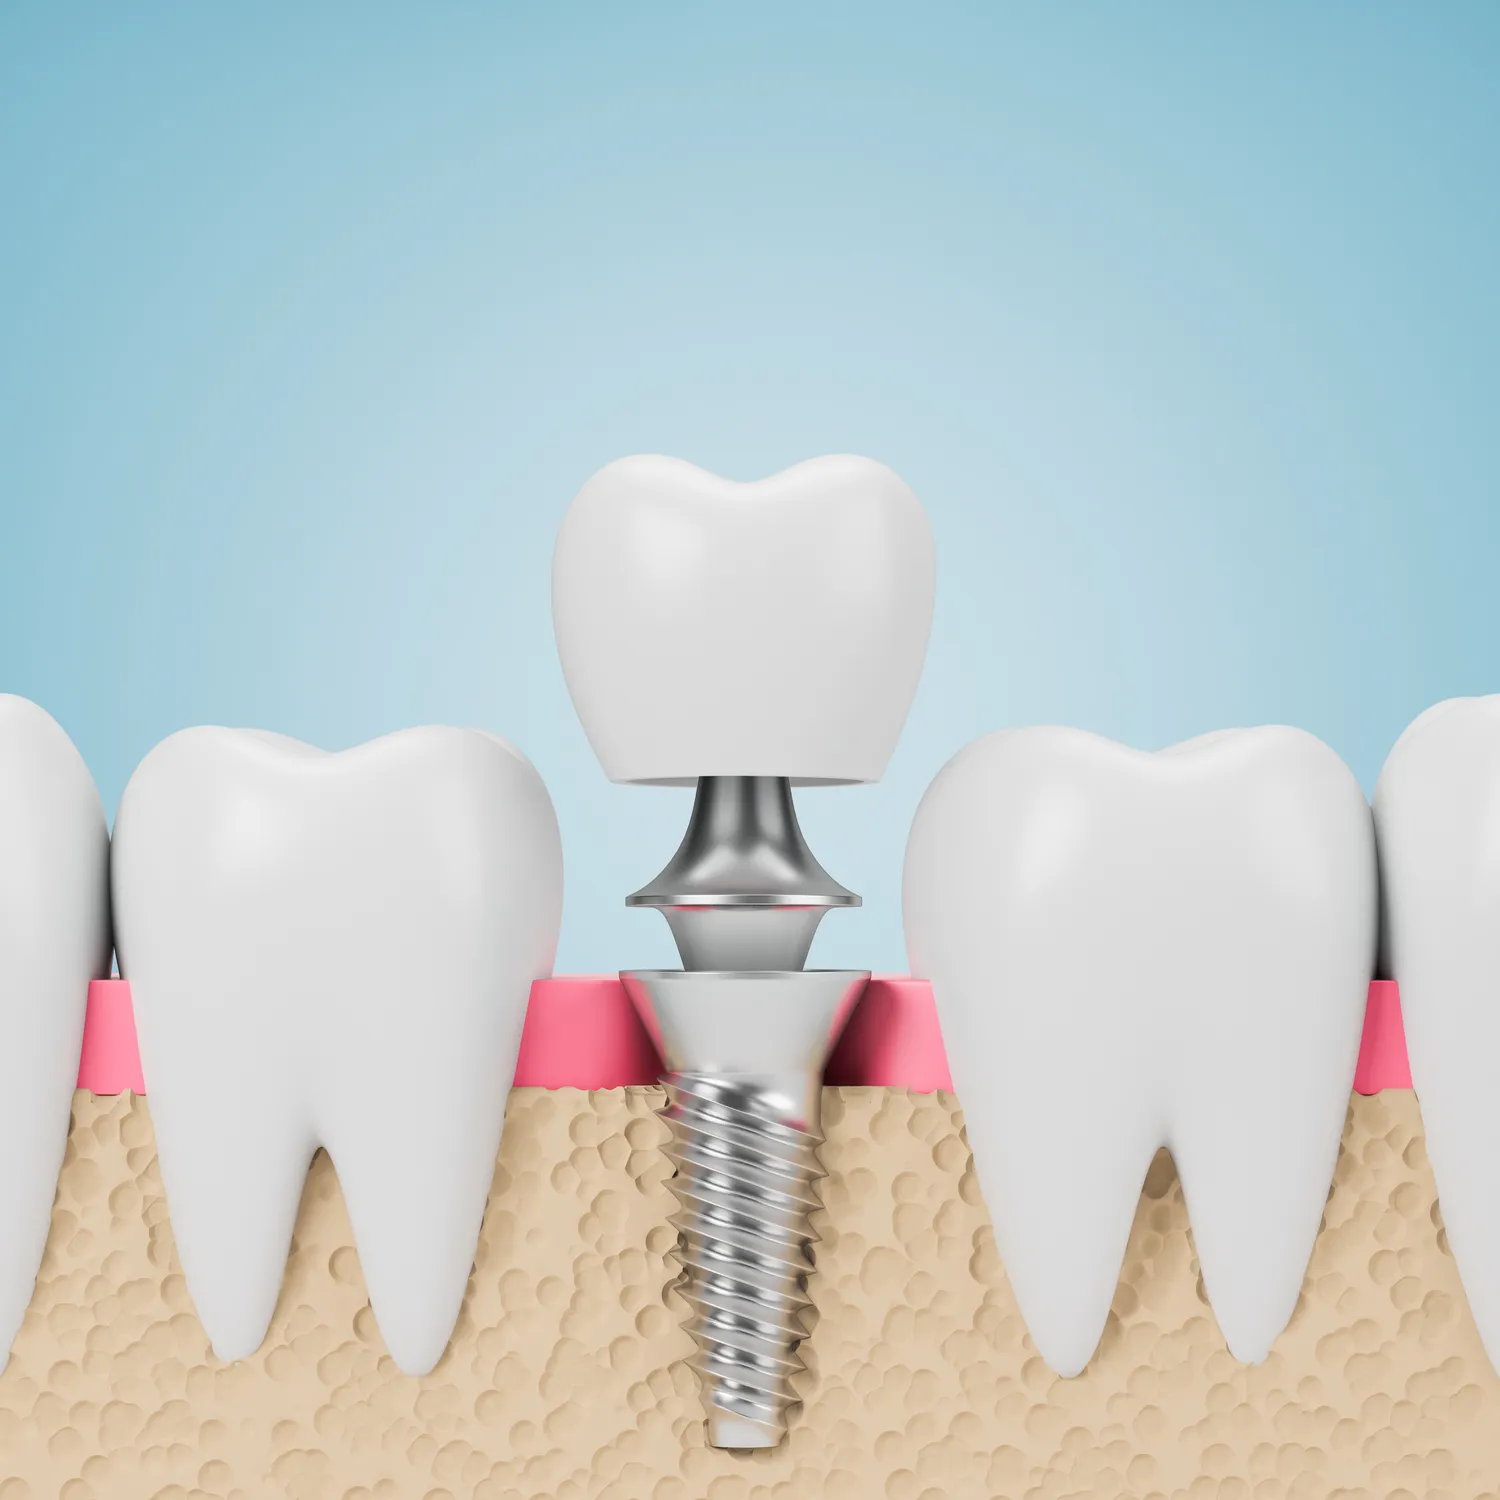

Implanty dentystyczne to jedna z najskuteczniejszych metod uzupełniania braków w uzębieniu, ale jak każda procedura medyczna, mają swoje zalety i wady. Do głównych zalet należy ich trwałość; przy odpowiedniej pielęgnacji mogą służyć przez wiele lat, a nawet całe życie. Implanty wyglądają i funkcjonują jak naturalne zęby, co znacząco wpływa na komfort życia pacjentów. Dodatkowo, wszczepienie implantu może zapobiegać utracie kości szczęki, która często występuje po ekstrakcji zęba. Warto jednak pamiętać o pewnych wadach; jednym z głównych ograniczeń jest koszt zabiegu, który może być znaczny. Nie każdy pacjent ma możliwość pokrycia wydatków związanych z implantami, a niektóre kliniki oferują jedynie drogie rozwiązania. Ponadto, proces wszczepienia implantu wymaga przeprowadzenia kilku etapów leczenia oraz czasu na gojenie się tkanek, co może być dla niektórych pacjentów uciążliwe. Istnieje także ryzyko powikłań, takich jak infekcje czy odrzucenie implantu przez organizm.

Prawidłowa pielęgnacja implantów dentystycznych po ich wszczepieniu jest kluczowa dla zapewnienia ich trwałości oraz zdrowia jamy ustnej. Po pierwsze, należy przestrzegać zaleceń lekarza dotyczących higieny jamy ustnej; codzienne szczotkowanie zębów oraz nitkowanie to podstawowe czynności, które pomogą utrzymać czystość wokół implantu. Warto również stosować płyny do płukania jamy ustnej zawierające antybakteryjne składniki; pomagają one zmniejszyć ryzyko infekcji wokół implantu. Regularne wizyty kontrolne u dentysty są równie ważne; lekarz będzie mógł ocenić stan implantu oraz otaczających tkanek miękkich i kości. Należy również unikać twardych pokarmów oraz nadmiernego obciążania implantu przez pierwsze miesiące po zabiegu; to pomoże uniknąć ewentualnych uszkodzeń czy przemieszczeń implantu. W przypadku wystąpienia jakichkolwiek niepokojących objawów, takich jak ból czy obrzęk wokół implantu, należy niezwłocznie skontaktować się ze swoim dentystą.